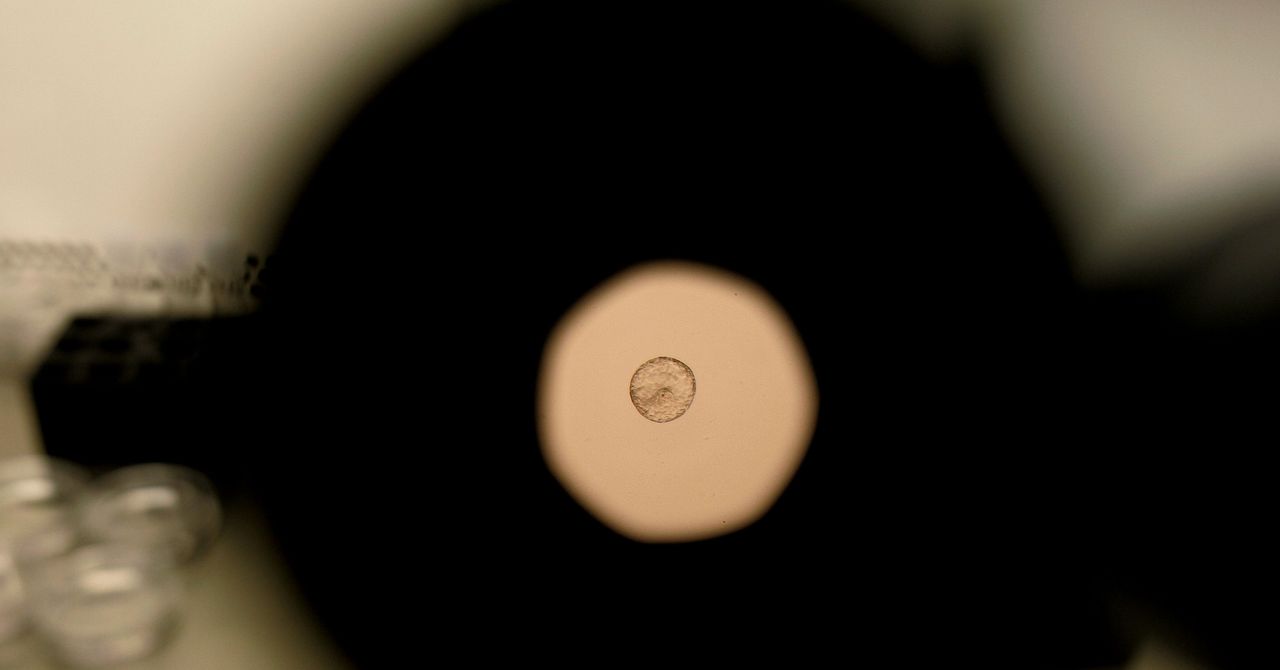

Video de lapso de tiempo del proceso de implantación de un embrión de ratón (izquierda) y un embrión humano (derecha).